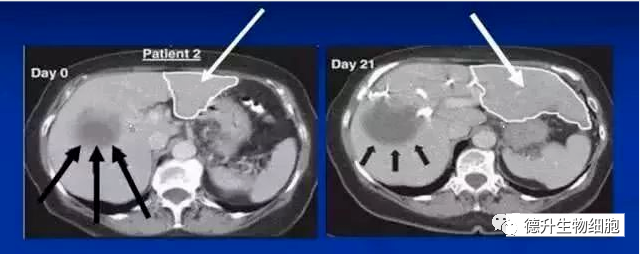

肝癌(肝右叶)部分肝切除患者,术前给予干细胞(CD133+)移植治疗(肝左叶),21天后肝左叶成倍增大。